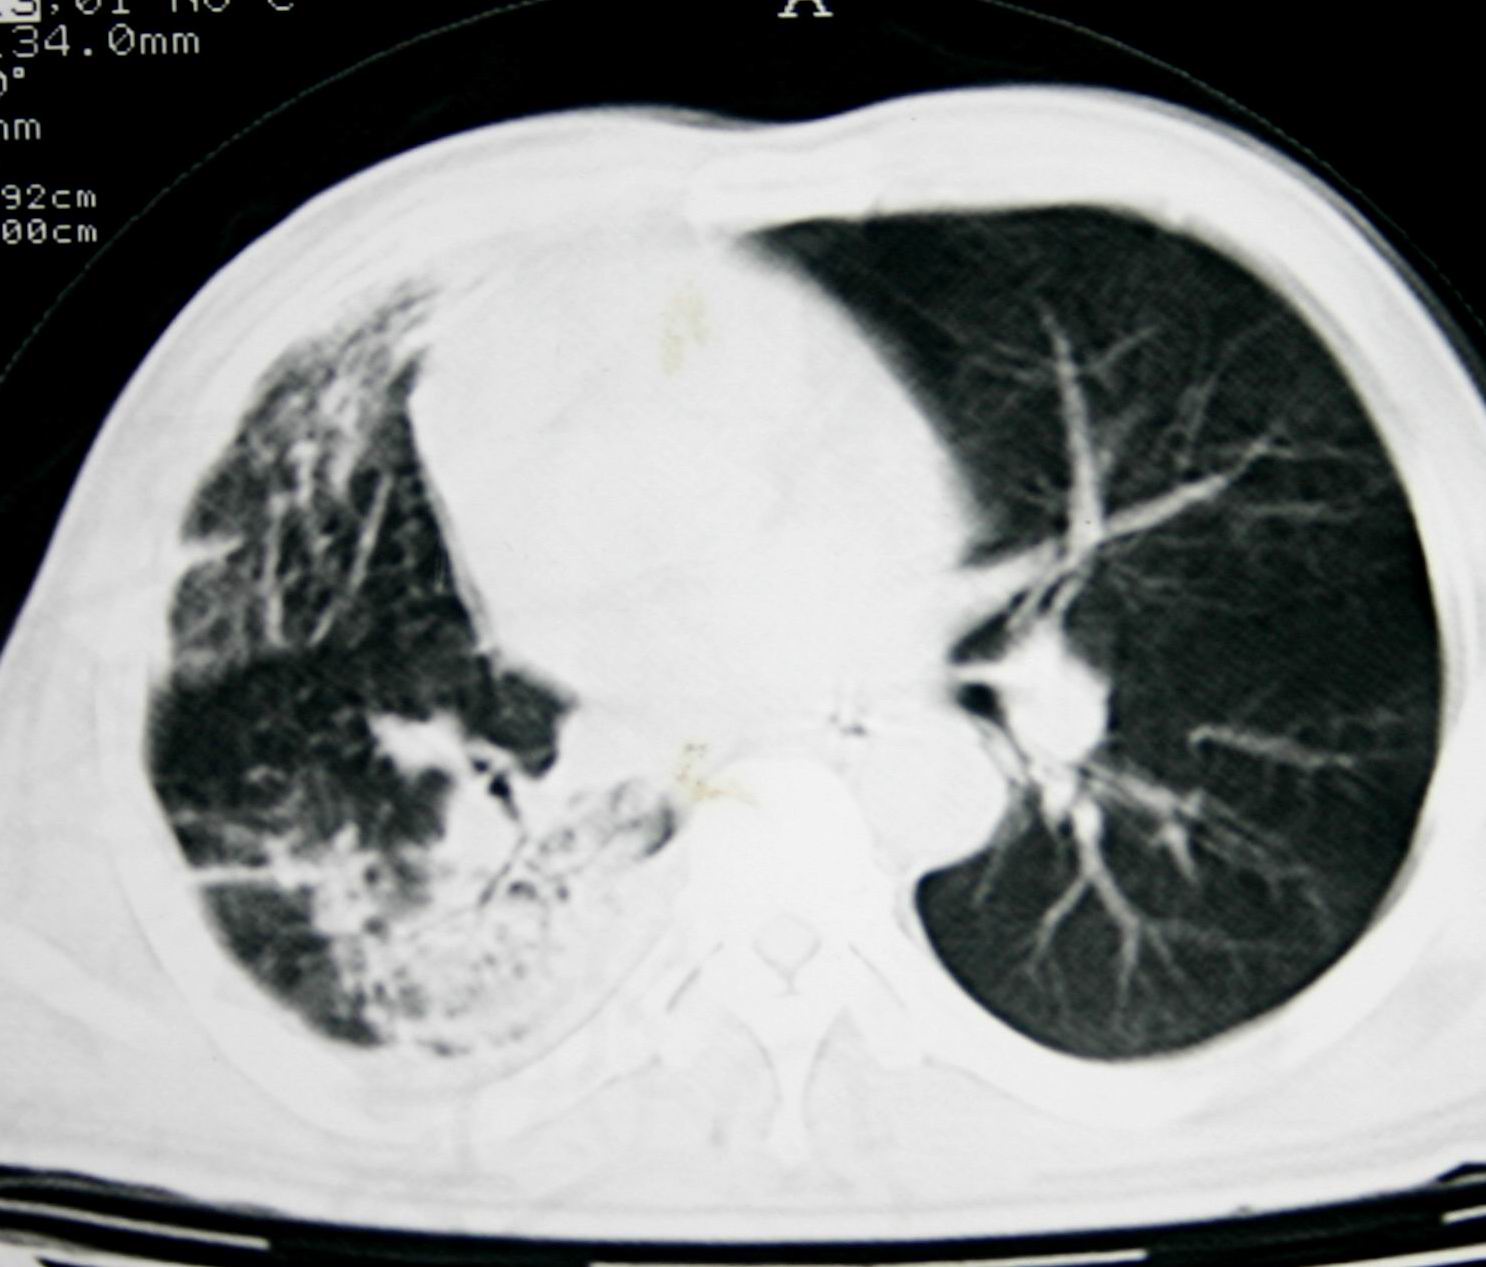

患者,男 ,48岁,反复咯血三个月,每三到五天咯一次,每次约200ml,鲜红色,无明显咳痰,咳嗽明显,无明显胸痛,无发烧,初期以抗感染、止血治疗,第一次ct报占位,支气管镜未见明显ca细,肺ca标志物、tb抗体均阴性,经过垂体后叶素、酚妥拉明、头胞他定、洛美沙星、立止血等治疗后,现病人一般情况好,停止咯血10天,咳嗽减少,咳黄脓痰,每日一次,每次30ml。现复查ct

右肺膨胀不全,纵隔右侧移位。肺内有感染,胸腔有积液。建议老片对比。

1)考虑右肺继发性肺结核合并感染。2)右侧胸腔积液+胸膜增厚。

支持:右肺膨胀不全,纵隔右侧移位。肺内有感染,胸腔有积液。建议老片对比。